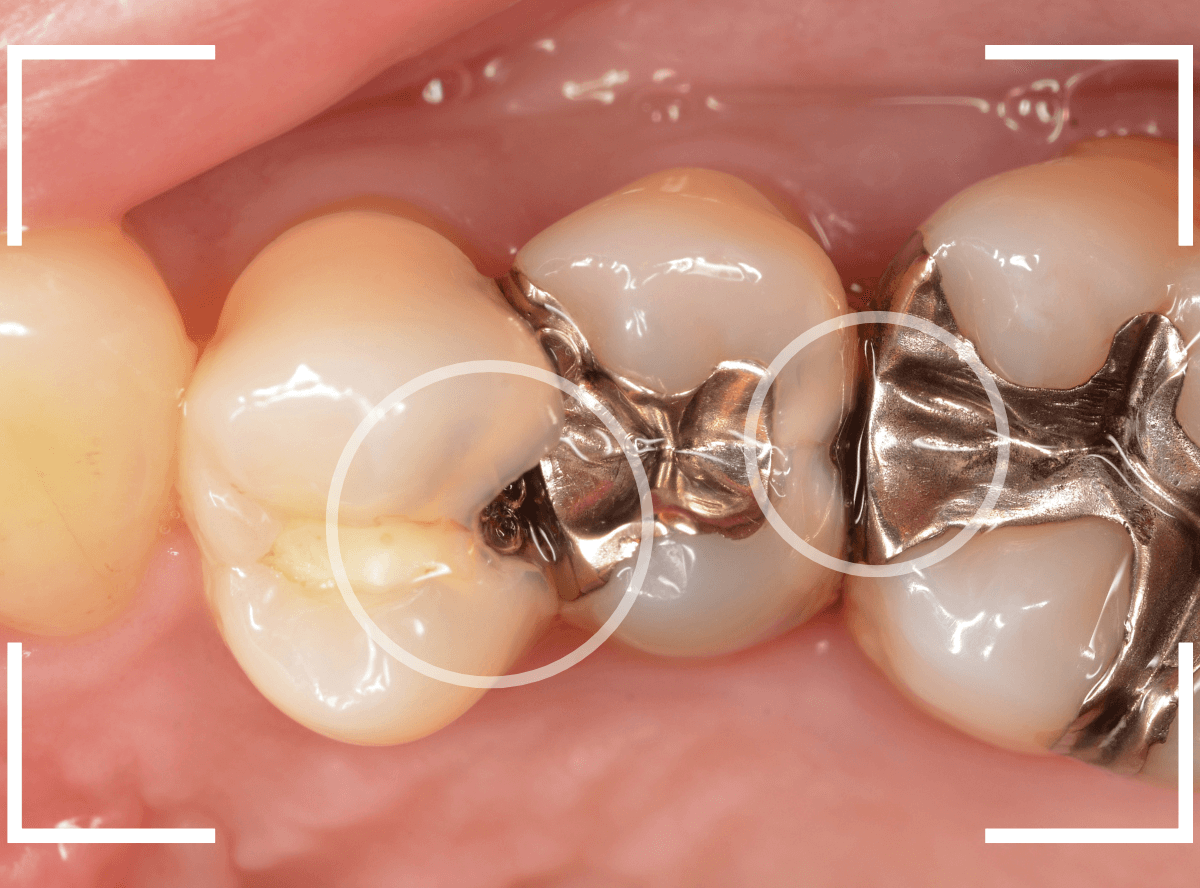

Case.7 定期メンテナンスで虫歯を発見!

メンテナンス時に、虫歯がみつかった患者さんです。

奥(右の〇)側が黒く虫歯が透けて見えますね、割とわかりやすい隣接面う蝕です。

よく見ると手前(左の〇)側も中が白濁してう蝕らしくなっているのがわかります。

レントゲン写真で確認します。

奥側の虫歯は明らかにレントゲンでも確認できますね、手前側の虫歯ははっきりしません。

あとは、虫歯を削りながら確認します。

まずは、奥側の部分から虫歯の治療をします。

少し削ると、落とし穴にはまるように虫歯の部分がでてきました。

最終的に虫歯を除去したところです。

奥の虫歯は、後ろの歯にまで及ぶ虫歯でした。

このように、隣りの歯との間の虫歯は、歯科医院での検査で初めてわかる事が多く、思ったよりも広く深い虫歯になっている事が多いです。

虫歯の深い部分にお薬をつめて経過観察後、隣りの歯をレジンで修復し、トリミング・型どりしました。

メタルインレーで最終修復したところです。

その後、症状もなく治療が終われました。